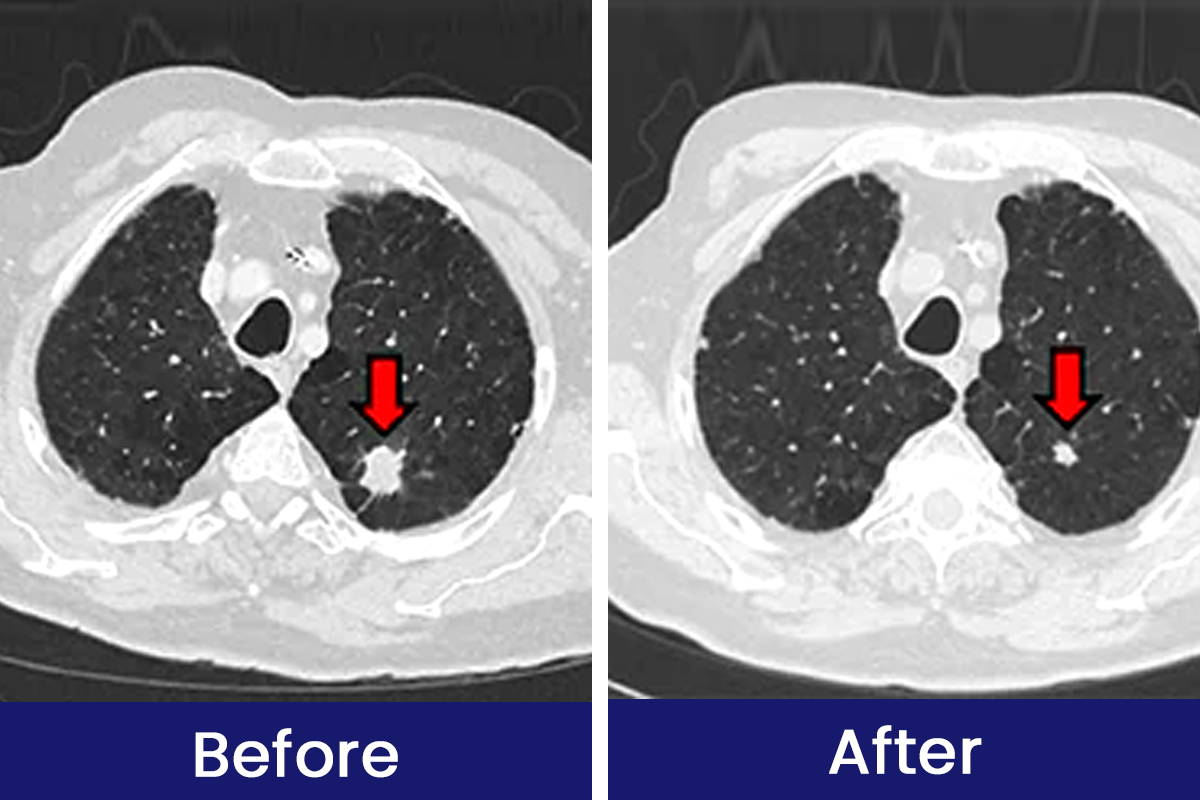

See How Luhaka™ Nicofree is Helping Customers Breathe Easier and Live Smoke-Free Every Day!